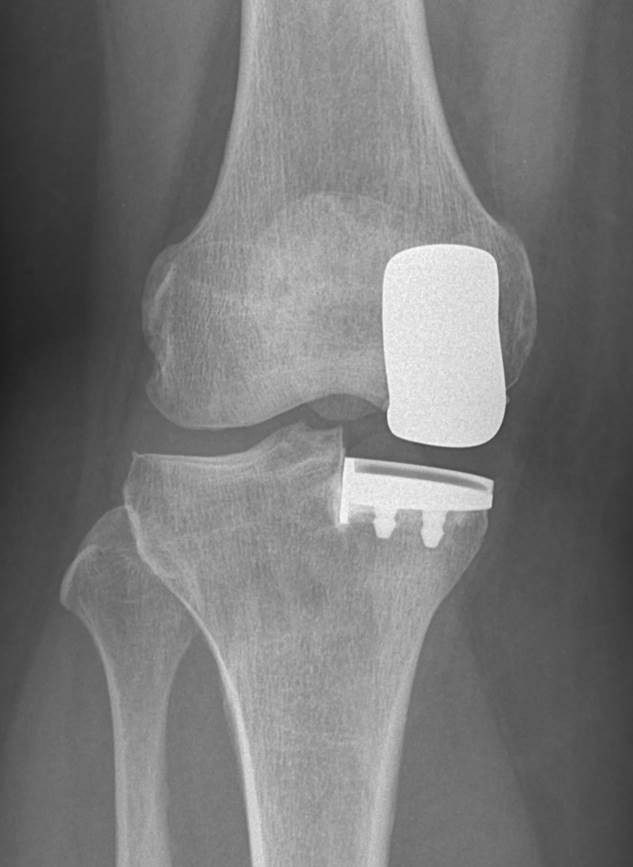

Innerer Teilgelenkersatz („Schlittenprothese“)

Wenn nur der Innere Anteil des Kniegelenkes von dem Verschleiß (Arthrose) betroffen ist, kann dies sehr gut durch eine sog. Schlittenprothese ersetzt werden. Diese kann über einen kleineren Schnitt, teils minimalinvasiv, implantiert werden ohne dass Muskulatur geschädigt wird. Hierbei bleiben alle Bänder des Kniegelenkes und der äußere Anteil der Gelenkfläche unversehrt.